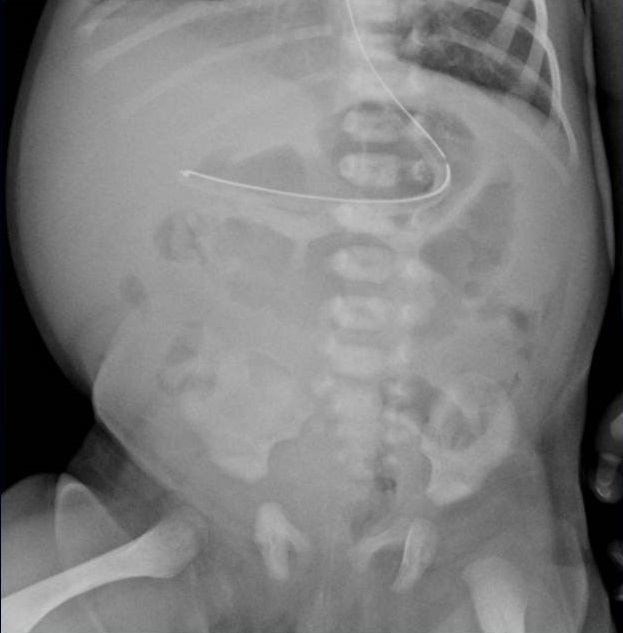

¿Cómo interpreta la radiografía abdomen?: